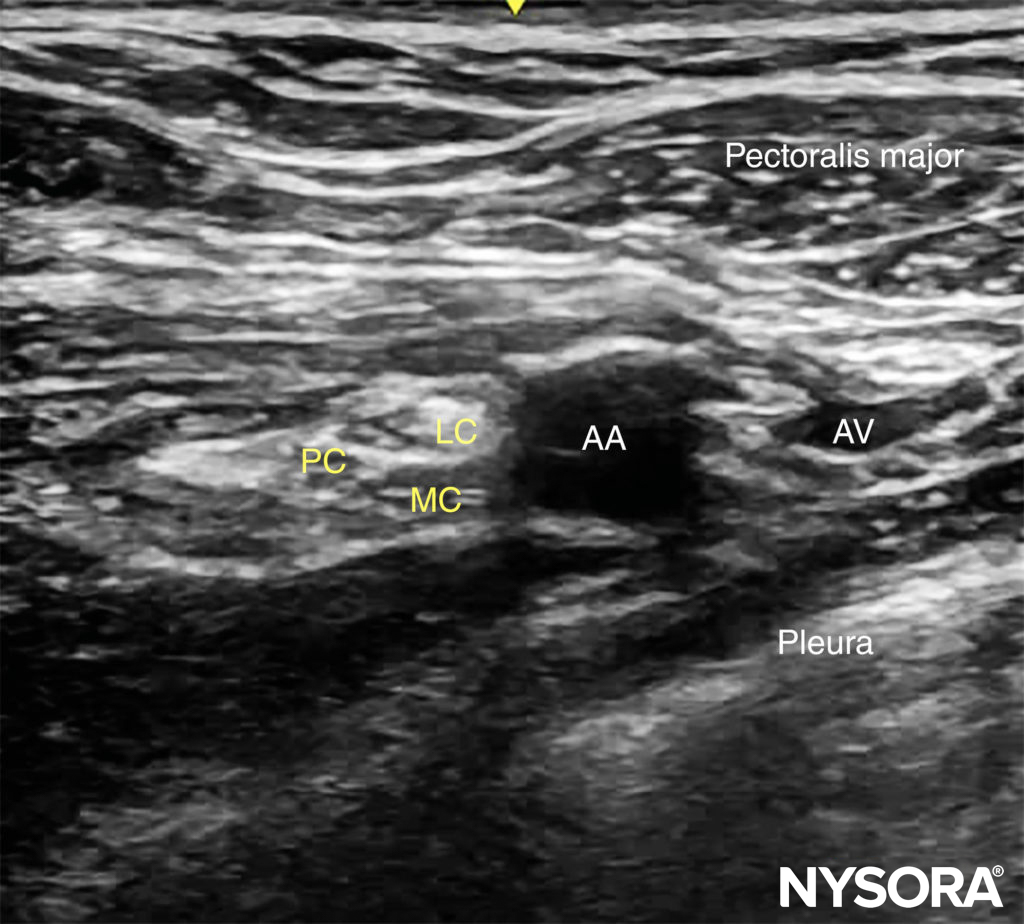

The axillary artery can be identified deep to the pectoralis major and minor muscles. An effort needs to be made to obtain clear views of both pectoralis muscles and their respective fasciae. This is important because the area of interest lies underneath the fascia of the pectoralis minor muscle. Surrounding the artery are the three cords of the brachial plexus: the lateral, posterior, and medial cords. These are named for their usual position relative to the axillary artery, although there is a great deal of anatomical variation. With the left side of the screen corresponding to the cephalad aspect, the cords can often be seen as round hyperechoic structures at the positions of approximately 9 o’clock (lateral cord), 7 o’clock (posterior cord), and 5 o’clock (medial cord) (Figures 2 and 3). The axillary vein is seen as a compressible hypoechoic structure that lies medially to the axillary artery. Multiple other, smaller vessels (eg, the cephalic vein) are often present as well. The transducer is moved in the cephalad-caudad and medial-lateral direction until the artery is identified in cross-section. Depending on the depth selected and the level at which the scanning is performed, the chest wall and the pleura may be seen in the medial and more caudal aspect of the image. The axillary artery and/or brachial plexus are typically identified at a depth of 3–5 cm in average-size patients.

FIGURE 3. Ultrasound image of the brachial plexus (BP) distal to the clavicle. Note that the BP, axillary artery (AA) and axillary vein (AV) are located below the fascia (red line) of the pectoralis minor muscle (PMiM). LC, lateral cord; MC, medial cord; PC, posterior cord; PMaM, pectoralis major muscle.

FIGURE 7. Ultrasound view of the brachial plexus at the costoclavicular space. The lateral (LC), medial (MC) and posterior (PC) cords are clustered together lateral to the axillary artery lying more superficial. At this level, the pectoralis minor is not seen deep to the pectoralis major.